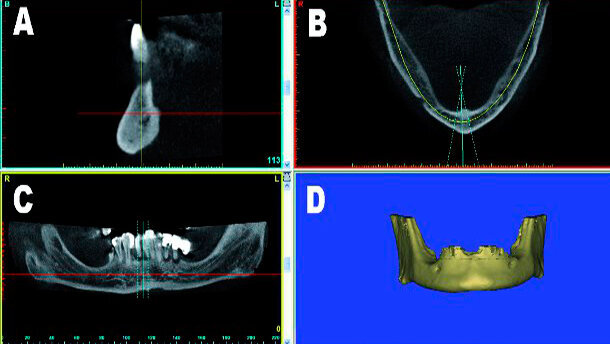

Mediante l’uso di modalità avanzate di imaging, si sono stabiliti nuovi paradigmi che, secondo l’opinione dell’autore, continueranno a ridefinire il processo di diagnosi e di pianificazione del trattamento circa le procedure implantari per gli anni a venire. Senza l’applicazione della tomografia computerizzata (CT) o della tomografia computerizzata cone beam a minor dosaggio (CBCT), non si può ottenere un’esatta comprensione della realtà anatomica tridimensionale, con aumento potenziale delle complicanze chirurgiche e restaurative. L’utilizzo di modalità di imaging in 3D come parte della pianificazione protesica pre-chirurgica può seguire diverse strade, come dimostrato nel diagramma di flusso. La prima prevede l’acquisizione di una scansione direttamente in 3D, senza alcuna pianificazione preventiva o apparecchiature accessorie. Il processo di scansione può essere realizzato in un centro di radiologia locale o tramite una macchina CBCT in studio, ora ampiamente disponibile. La scansione in sé può essere completata in pochi minuti. Una volta che i dati sono stati elaborati, possono essere visualizzati mediante il software della macchina CBCTutilizzata e valutati per potenziali siti riceventi implantari, seguìti dall’intervento chirurgico. Un secondo percorso richiede la realizzazione di un dispositivo scanner radiopaco che incorpora informazioni restaurative vitali e che sarà indossato dal paziente durante l’acquisizione della scansione. In questo modo si può valutare la posizione dei denti rispetto all’osso sottostante e ad altre importanti strutture anatomiche, come il seno mascellare o il nervo alveolare inferiore. Si possono visualizzare di nuovo i dati di scansione tramite il software originale della macchina CBCT e si può decidere un piano basato direttamente sulle esigenze restaurative del paziente.